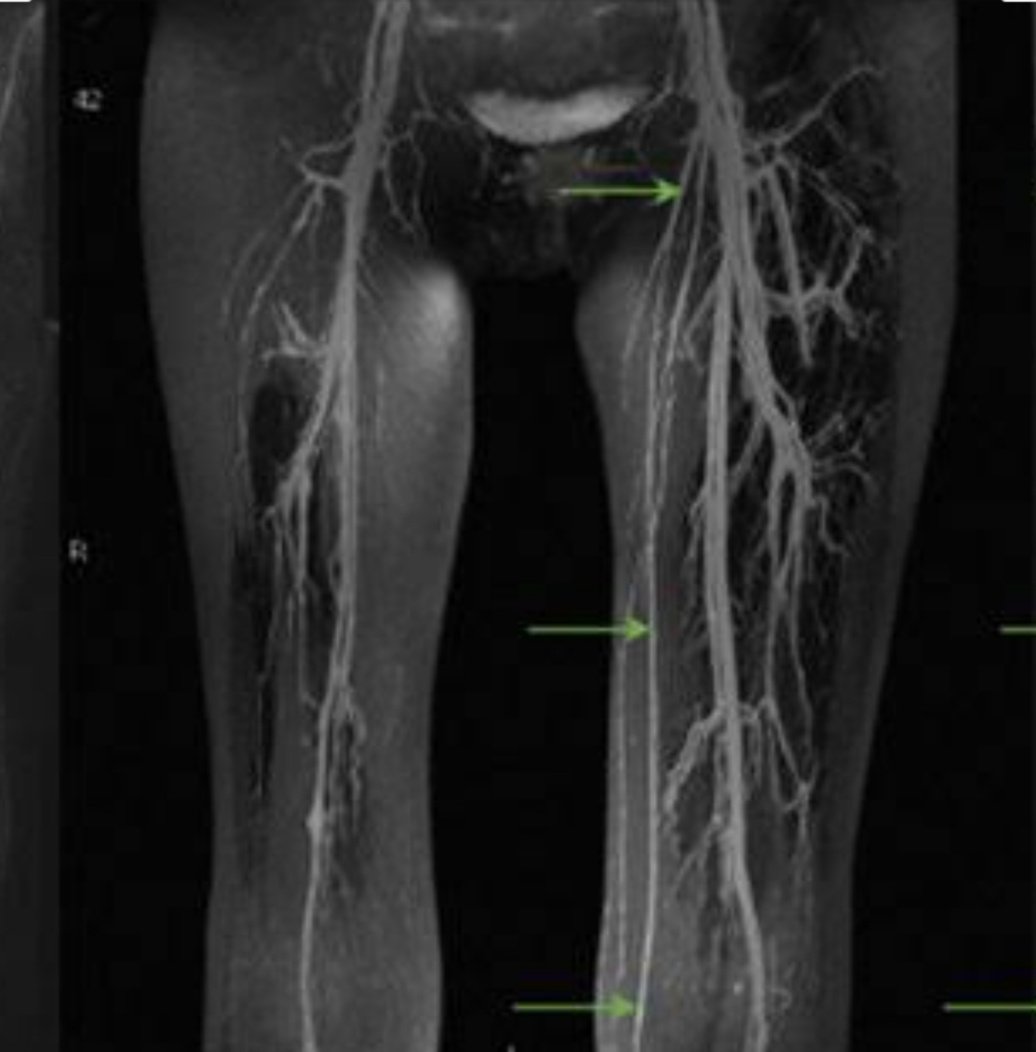

Кт вен таза

Кт вен таза 96 фотографий